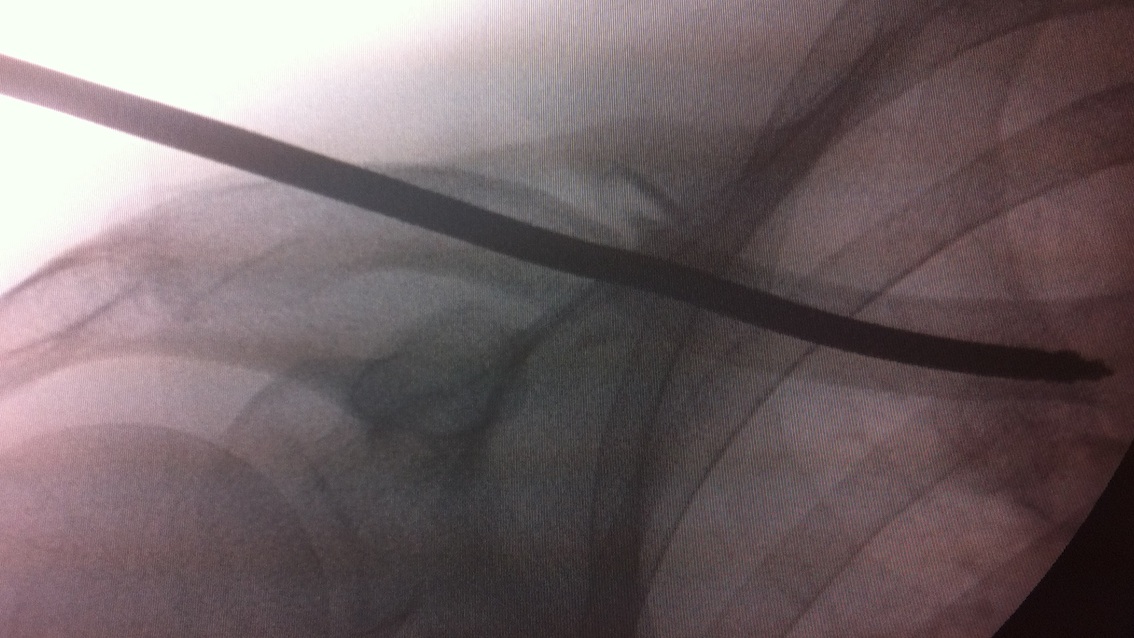

Technique

Vumedi surgical technique clavicle IM screw

Mini open approach to fracture

- drill medial fragment for screw

- pass cannulated wire through lateral fragment and out through skin

- reduce fracture and pass wire into medial fragment

- drill lateral fragment

- insert cannulated 6.5 mm screw

- needs to be between 80 and 110 mm

- check x-ray to ensure good medial fixation